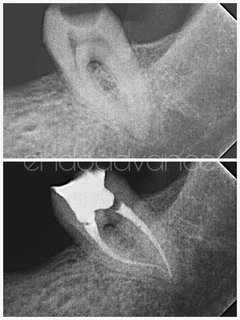

Αρχική ενδοδοντική θεραπεία σε 2ο κάτω γομφίο με μορφολογία C-shaped